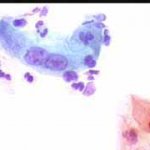

Περιστατικό ασθενούς που παρακολουθείται στο ιατρείο μας από το 1993, τότε ηλικίας 37 ετών, αρχικά λόγω ασυμπατωματικού κυτταρολογικά εμμένοντας έρπητος τραχήλου της μήτρας. Το γεγονός αυτό μας οδήγησε στην διερεύνηση της περιπτώσεως. Η ασθενής επασχε από A.I.D.S.

Είχαμε την ευκαρία να παρακολουθήσουμε ανά 6μηνο γυναικολογικά, κολποσκοιπικά και κυτταρολογικά την γυναίκα από το 1993 μεχρι και το 2008. Από τις εξετασεις αυτές, παρουσιάζουμε χαρακτηριστικές κυτταρολογικές εικόνες . Όι παρακάτω κυτταρολογικές εικονες προέρχονται από την 2η κατά σειρά εξέταση της ασθενούς το 1993. Οι κυτταρολογικές αλλοιώσεις ερπητος συνεχίζουν να υφίστανται.

Ακολουθουν κυτταρολογικές εικονες από τα έτη 1997 - 1998.